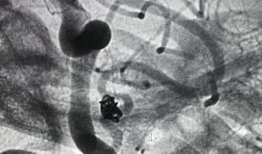

造影视频全过程,揭示血管奥秘与诊疗过程

你知道吗?最近我在网上看到一个超级有趣的造影视频全过程,简直就像是一部迷你电影,让我忍不住想要和你分享一下。这个视频详细记录了整...